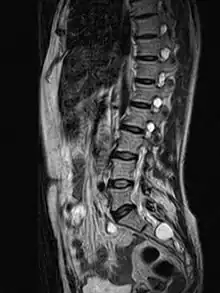

MRI image showing a Tarlov cyst

MRI sagittal image of sacral and dorso-lumbar perineural cysts.

MRI, or Magnetic Resonance Imaging, is considered the imaging study of choice in identifying Tarlov cysts. MRI provides better resolution of tissue density, absence of bone interference, multiplanar capabilities, and is noninvasive. Plain films may show bony erosion of the spinal canal or of the sacral foramina. On MRI pictures, the signal is the same as the CSF one.